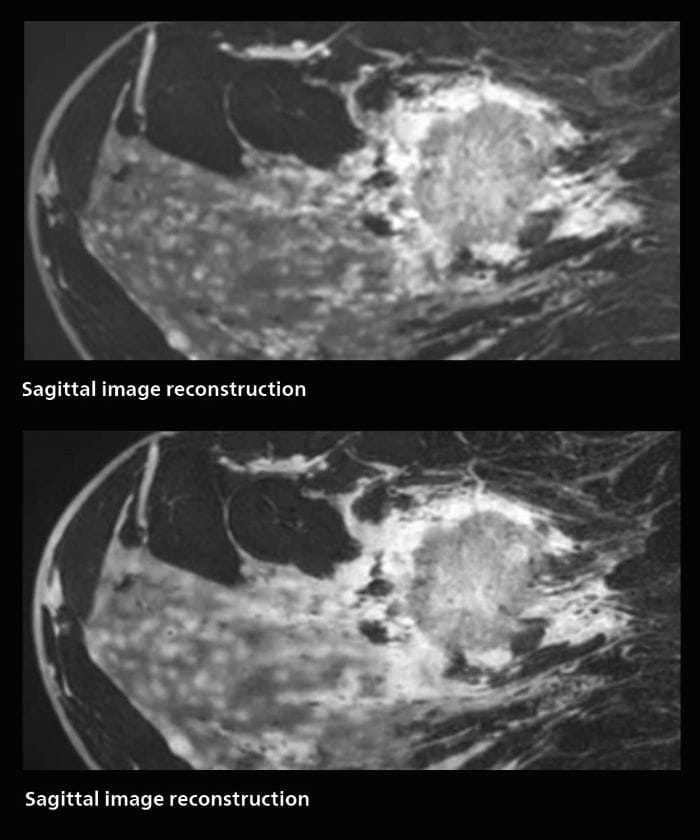

3D MRI of breast cancer

Scanning was performed with two different voxel sizes. AI enabled volume MRI allows image reconstruction in other directions. Biopsy revealed invasive ductal carcinoma in this patient. Performed on Elition X.

Fast AI-enabled MRI of breast cancer: comparing 3D acquisitions with 0.75 mm and 0.6 mm isotropic voxels.

Speed and high image quality are also important factors determining the diagnostic value of breast MRI. “When the spatial resolution is not high enough for making the diagnosis of breast cancer, a very difficult decision must be made,” says Dr. Katahira. “Since SmartSpeed now allows us to increase the resolution, we can often easily provide a confident answer. In the past with SENSE we used 1.2 mm isotropic voxels in breast imaging after contrast admission. With Compressed SENSE that is 0.8 mm. Now with SmartSpeed we can acquire 0.6 mm isotropic voxels and the images are so clear that even tiny details are clearly visible.”

“The use of SmartSpeed has considerably improved our breast cancer imaging, with higher temporal resolution, higher spatial resolution, and higher SNR compared to the past, when we were using just Compressed SENSE. In addition, the dynamic study is now more useful in diagnosis because the ultrafast dynamic scan can be taken every 3 seconds.”